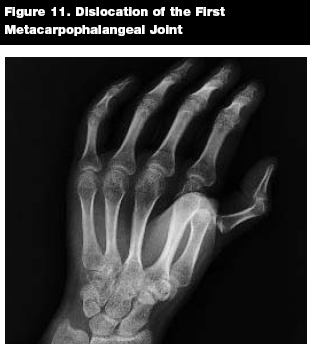

Metacarpophalangeal Dislocations

Epidemiology. Metacarpophalangeal (MCP) joint dislocation is not common, but it can be a serious injury that is typically associated with significant trauma.28 The index finger and thumb are the most commonly involved digits.15,28 (See Figure 11.) Even so, MCP dislocation of the thumb in children is rare.29

![]() |

Patterns of Injury. Outdoor and sporting injuries are a common cause for MCP dislocations in children. Hyperextension and falls on an outstretched hand are common causes.30 Dislocations may be classified as simple or complex, with the latter involving soft tissue interposition between the articular surfaces of the joint. In the complex dislocation, the soft tissue trapped between the dislocated articular surfaces can sometimes prevent successful closed reduction.15,30

Evaluation. As with all hand injuries, a thorough neurovascular exam should be completed. The physical exam in MCP dislocation injuries can appear benign, even with severe injuries. The MCP joint is usually held in extension, while the IP joints are flexed. Skin dimpling on the palmar surface of the digit over the metacarpal head can be diagnostic of MCP dislocation.13,28

Imaging. Radiographs of the injured hand will reveal the dislocation and any associated fractures. A sesamoid bone seen in the joint is diagnostic of a complex dislocation.13

Management. Dorsal finger dislocations of the MCP joint are managed similarly to IP joint dislocations, with distal traction and volar pressure on the dislocated bone.15 Splint the joints in flexion, and refer to a hand surgeon. Closed reduction is successful about 50% of the time.31 Management of irreducible dislocations should be deferred to a hand surgeon.

Thumb MCP dislocations are rare injuries that usually require referral to a hand surgeon.32 An attempt at closed reduction can be made, however. A thumb spica splint should be placed with the MCP joint in 20° of flexion following successful reduction.13,15

Key Points. MCP joint dislocations are uncommon injuries in children. Simple dorsal dislocations are often successfully reduced by the emergency physician. Injuries may need to be treated by a hand surgeon if the attempted reduction is not successful.